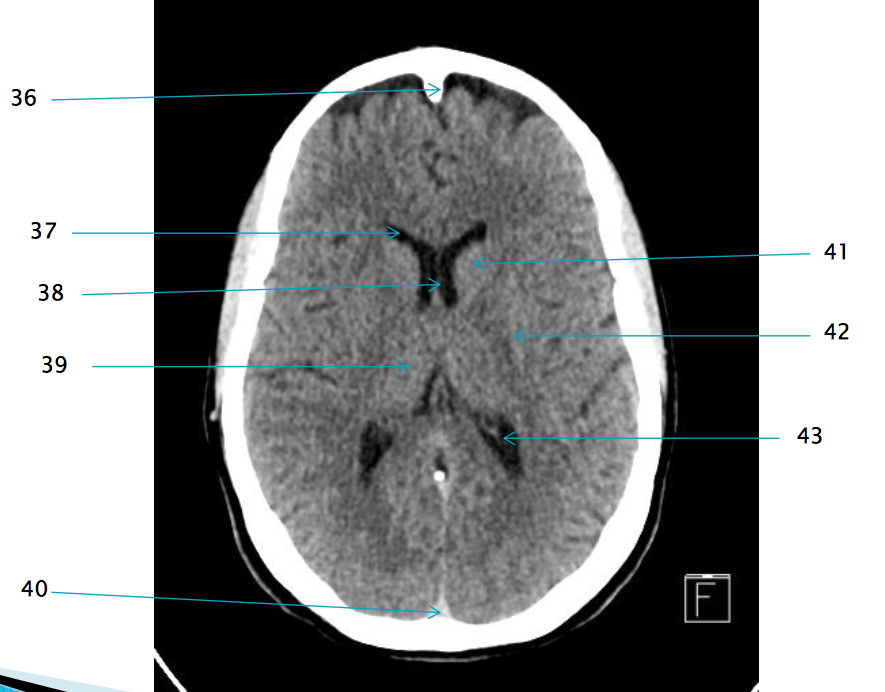

35

Superior sagittal sinus

37

Frontal horn of R lateral ventricle

38

Septum pellucidum